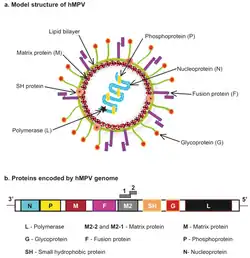

Genome

The genomic organisation of HMPV is similar to RSV; however, HMPV lacks the non-structural genes, NS1 and NS2, and the HMPV antisense RNA genome contains eight open reading frames in slightly different gene order than RSV (viz. 3’-N-P-M-F-M2-SH-G-L-5’).[35] HMPV is genetically similar to the avian metapneumoviruses A, B and in particular type C. Phylogenetic analysis of HMPV has demonstrated the existence of two main genetic lineages termed subtype A and B containing within them the subgroups A1/A2 and B1/B2 respectively. Genotyping based on sequences of the F and G genes showed that subtype B was associated with increased cough duration and increased general respiratory systems compared to HMPV-A.[36]